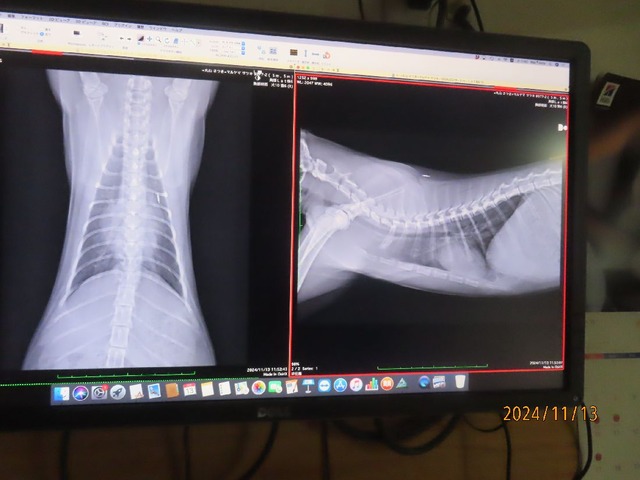

呼吸についてはレントゲンを撮って貰いましたが、異常は見られずきれいなものだそうです。

様子見でいいとのことです。ななんかそんなんばっかりです。